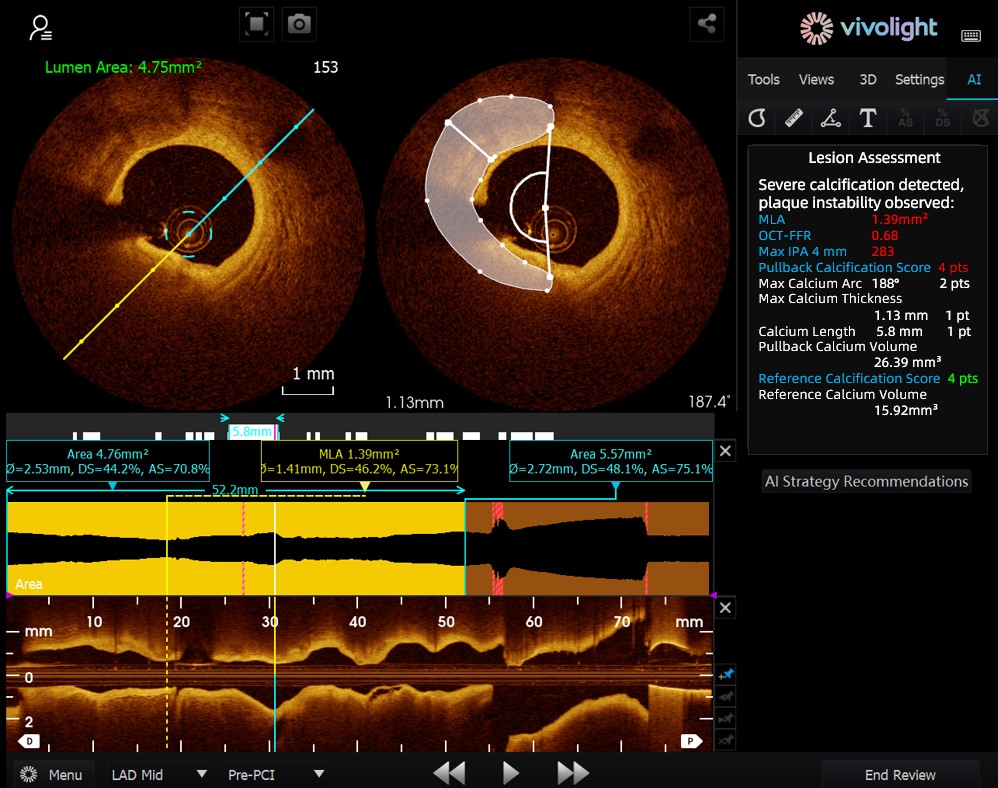

Das auf dem OCT-System von Vivolight Medical basierende AI-OCT ist ein intelligentes Entscheidungsunterstützungssystem der nächsten Generation für die intravaskuläre Bildgebung. Es integriert verstreute intravaskuläre Bildgebungsdaten – darunter Lumendurchmesser, ursächliche Läsionen, OCT-FFR und Plaquebeschaffenheit – in umfassende Behandlungsstrategien und umsetzbare Empfehlungen. Als eigenständige Forschungssoftware, die in die OCT-Plattform integriert ist, wird sie in Zusammenarbeit mit verschiedenen Krankenhäusern entwickelt, um kundenspezifische Versionen für spezifische klinische Bedürfnisse zu erstellen.

Auf dem hochkarätigen Forum betonten Experten, dass das KI-OCT-System einen grundlegenden Wandel von der reinen Bildbetrachtung hin zur Erstellung von Behandlungsplänen darstellt. Es begegnet den Herausforderungen der Informationsflut und der komplexen Entscheidungsfindung bei kardialen Interventionen, die traditionell stark auf der Erfahrung des Arztes beruhen. Zu den wichtigsten Vorteilen des Systems zählen:

●Intraoperative Echtzeitführung: Es organisiert diagnostische Informationen dynamisch während der Operation und liefert wichtige Kennzahlen und klinische Empfehlungen.

●Evidenzbasierte Entscheidungsfindung: Alle Vorschläge entsprechen dem Expertenkonsens und den klinischen Leitlinien, wodurch Strenge und Zuverlässigkeit gewährleistet werden.

Das KI-OCT-System nutzt eine Architektur aus „kleinen Modellen + großen Datenmengen + großen Modellen“: Kleine Modelle ermöglichen eine präzise Bildinterpretation, während große Modelle umfassende klinische Schlussfolgerungen ermöglichen. Durch die Nutzung hochwertiger kardiovaskulärer Datenbanken und der Retrieval-Augmented Generation (RAG)-Technologie bietet es durchgängige Unterstützung von der Läsionsbeurteilung bis zur Entwicklung von Behandlungsstrategien.